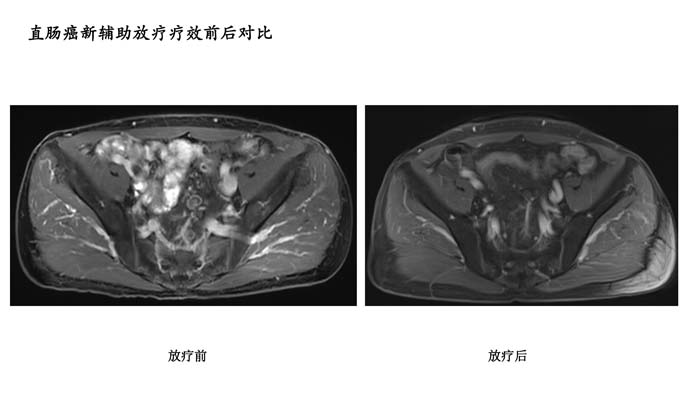

直肠癌新辅助放疗疗效前后对比2

- 直肠癌新辅助放疗疗效前后对比2